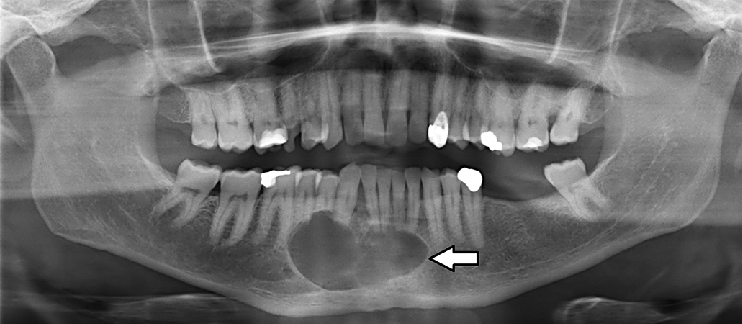

- Ακτινογραφίες: Συνήθως πανοραμική ακτινογραφία για την απεικόνιση της δομής της γνάθου.

Το αδαμαντινοβλάστωμα συνήθως εντοπίζεται στην κάτω γνάθο, αν και μπορεί να εμφανιστεί και στην άνω. Αποτελεί περίπου το 1% όλων των όγκων της γνάθου και εμφανίζεται συχνότερα σε ενήλικες ηλικίας 30-40 ετών. Παρόλο που δεν είναι καρκινικός, ο όγκος μπορεί να είναι τοπικά επιθετικός και να προκαλέσει βλάβη στον περιβάλλοντα ιστό.